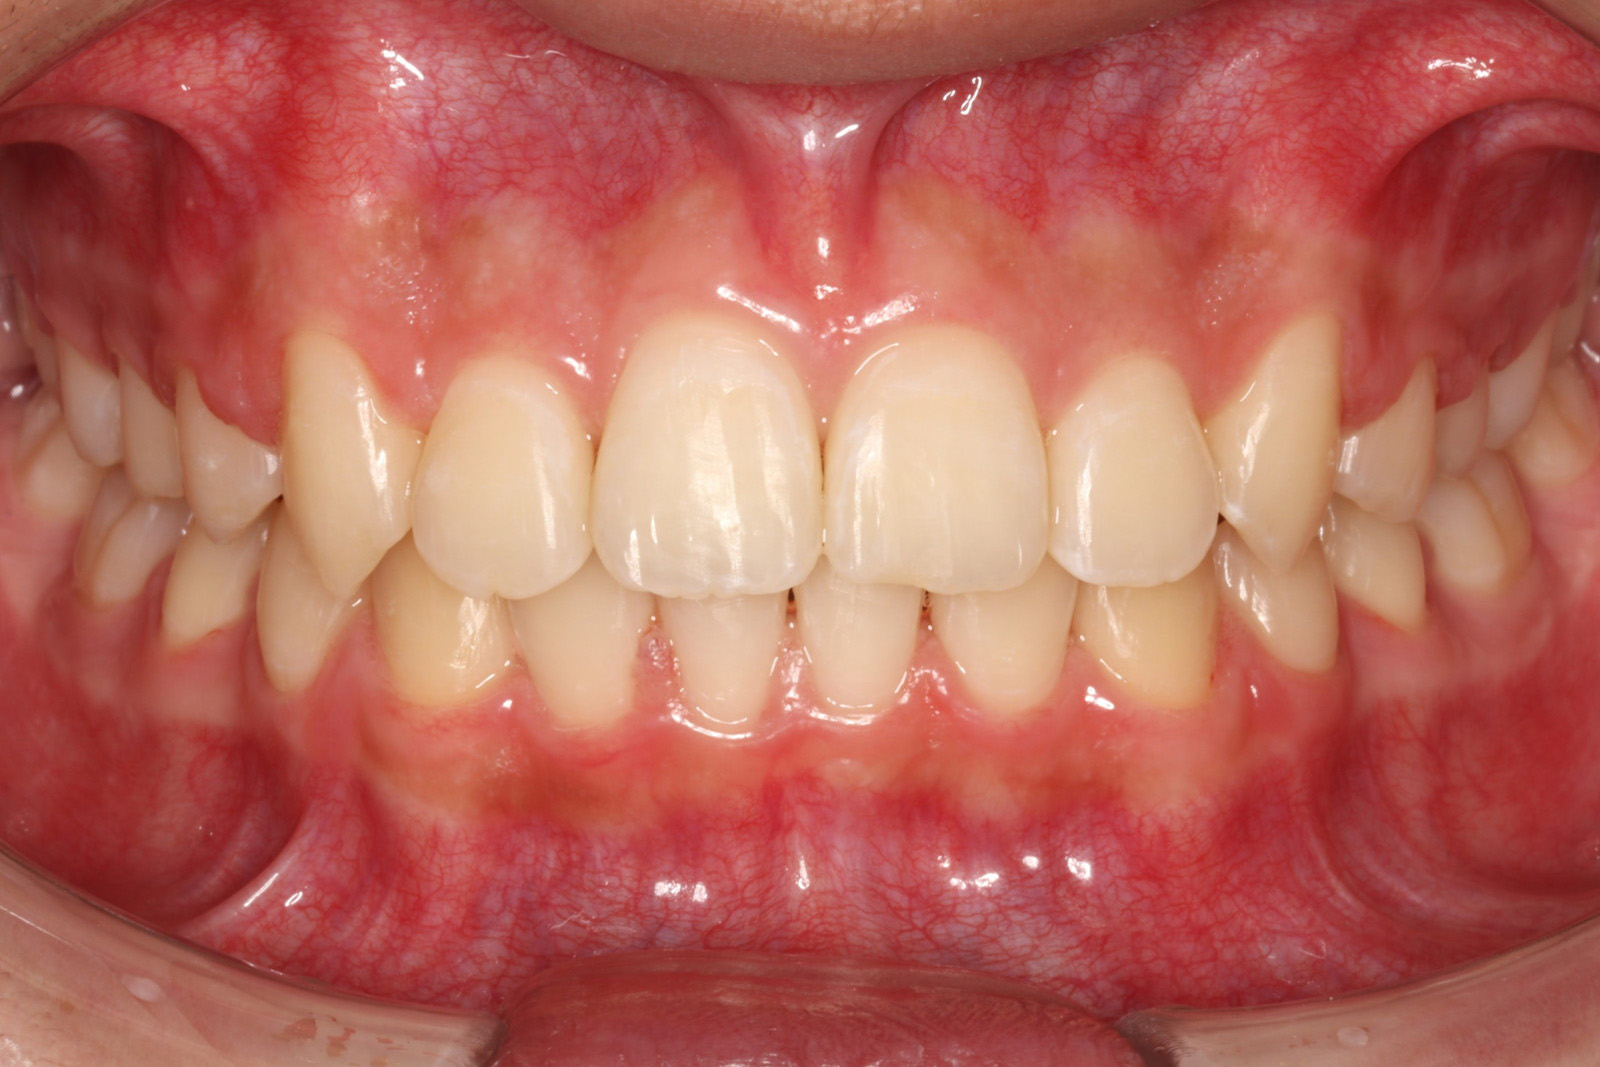

問診を行い、お口の悩みや希望を確認します。レントゲン撮影や口腔内写真の撮影など、必要に応じた精密検査を行います。

検査結果に基づき、現在の状態と治療計画(期間や費用含む)についてご説明します。